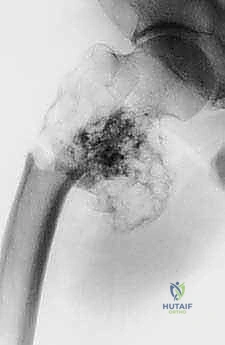

| الأشعة السينية (X-rays) | التقييم الأولي السريع لشكل العظم، اكتشاف الكسور المرضية، وتحديد نمط تدمير العظم. | تعطي الجراح فكرة عامة عن حجم المشكلة وموقعها. |

* الساركوما العظمية (Osteosarcoma): الورم الأكثر شيوعاً، يظهر غالباً في منطقة الركبة (أسفل الفخذ أو أعلى القصبة). يتطلب استئصالاً واسعاً مع هوامش آمنة (إزالة جزء من العظم السليم المحيط بالورم لضمان عدم ترك خلايا سرطانية).

تؤدي هذه الأورام إلى تآكل العظم، مما يسبب ألماً مبرحاً ويجعله عرضة لما يسمى "الكسر المرضي" (انكسار العظم نتيجة إجهاد بسيط جداً بسبب هشاشته الشديدة). في هذه الحالات، يتم استئصال الجزء المدمر واستبداله بطرف اصطناعي لتخفيف الألم فوراً والسماح للمريض بالمشي مجدداً.

بعض الأورام الحميدة، مثل "الورم ذو الخلايا العملاقة" (Giant Cell Tumor)، رغم أنها لا تنتشر إلى أعضاء أخرى، إلا أنها تنمو بشراسة موضعياً وتدمر المفصل والعظم المحيط به. إذا كان التدمير واسع النطاق، يكون الاستئصال وإعادة البناء هو الحل الأفضل.